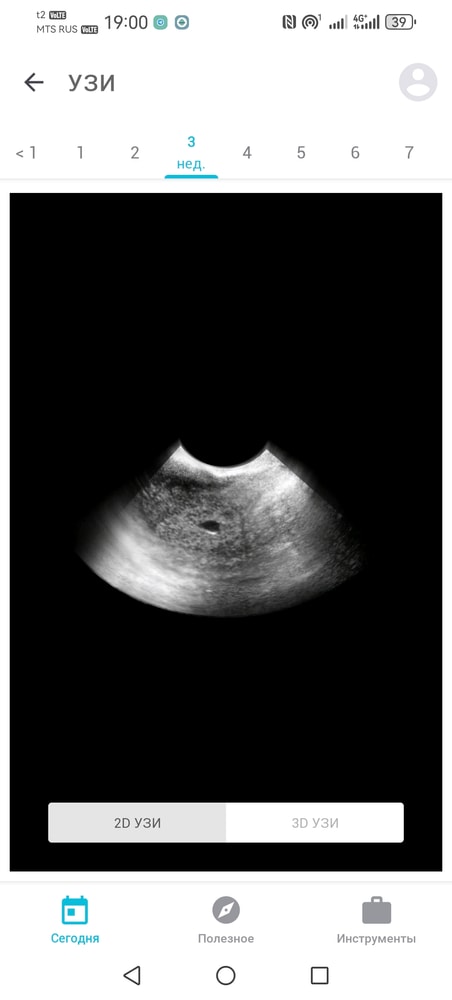

На узи сходила в 6 недель и 2 дня по календарю, нашли пя 3,9мм и желточный мешочек 1,2мм. Узистка сказала что должно быть 6 недель и 2 дня, но по узи всего 3, возможно из-за поздней овуляции (на узи просто видно было как чёрное пятнышко и всё). Тогда кровь на хгч не сдавала.

Bandy, так вроде бы как и похоже по размеру, на 5 недель вроде не тянет эта чёрная точечка. Вообщем как-то всё сложно, несколько дней голову ломаю, побыстрее бы уже получить результат второго хгч

Анастасия, как раз на 5 недель и тянет. Где указан срок 3 недели - это то же самое что 5 в акушерстве.